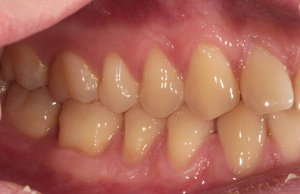

Спасибо всем большое. Дождался заказной вспышки и внутриротовых зеркал с контрастерами.

Все прблемы ушли. Конфигурация техники: Кэнон 550, объектив Кэнон 100/2.8 макро, вспышка Макро

МТ-24ЕХ, зеркала металл YDM.

Ещё. Какие замечания по настройкам?горизонт завален...